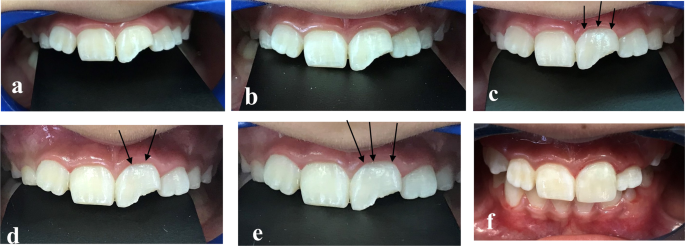

The mean ĪE value at 12 months in the WMTA group was (ĪEā=ā3.64ā±ā2.31) and NeoMTA group was (ĪEā=ā2.99ā±ā2.56). No statistically significant difference between both materials during the 12 months (p value = 0.535). Mean values for ĪE are presented in Fig.Ā 4. Clinical photographs showing the evaluation of discoloration in Group (N) and (W), Figs.Ā 5 and 6.

a Baseline clinical photograph of upper left central incisor at second appointment, b Clinical photograph at 1 week follow up without discoloration, c Clinical photograph at 1 month follow-up showing shadow of cervical crown discoloration, d Clinical photograph at 3 months follow-up showing cervical crown discoloration, e Clinical photograph at 12 months follow-up showing cervical crown discoloration. f Clinical photograph showing composite buildup.